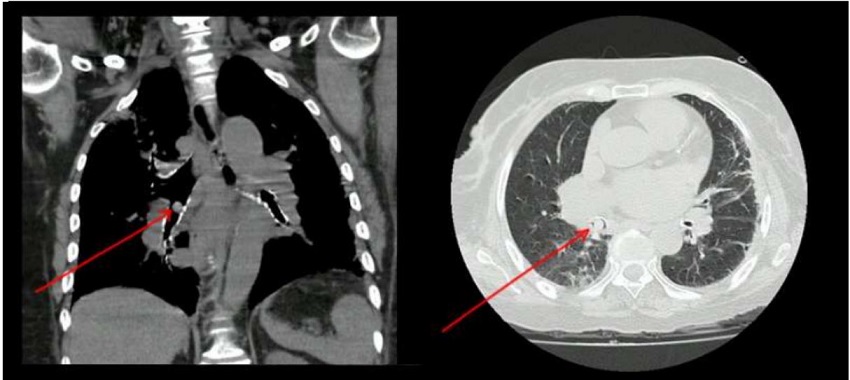

De acuerdo con los exámenes paraclínicos de ingreso, se registró: química sanguínea normal y reactante de fase aguda elevado; gases arteriales con trastorno moderado de la oxigenación con presión arterial/fracción inspirada de 200 mmHg. La figura 1 muestra los resultado de la tomografía axial computarizada (TAC) de tórax que se le tomó.

Luego de los resultados del TAC, a la paciente se le realizó una fibrobroncoscopia, pues se había documentado que en el bronquio intermediario había un objeto que obstruía la totalidad de la luz. Así, se le extrajo el elemento con una canastilla de cuerpo extraño, que fue retirado de forma completa en un único intento (figura 2). Adicional a ello, se le realizó un lavado broncoalveolar, que evidenció una secreción purulenta, por lo que se inició cubrimiento antibiótico. Después de lo anterior, fue valorada por el servicio de fonoaudiología, que le practicó una prueba deglutoria, cuyo resultado fue consistencia líquida total espesa sin grumos. Además, se le encontró una alteración moderada de la función oral-faríngea de la deglución en fase oral/voluntaria.